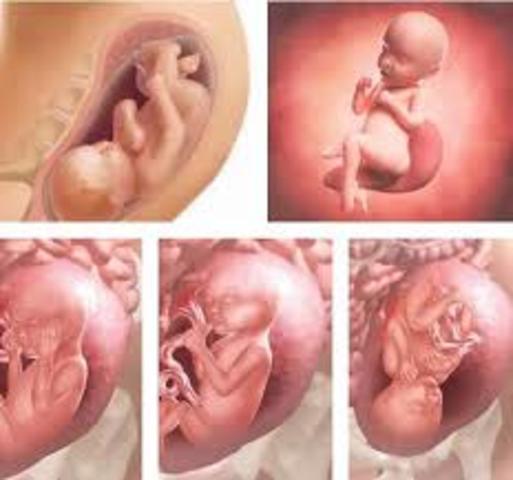

El embarazo se mide en semanas a partir de la última regla, pero el bebé se concibe antes. A partir de la semana 2 del embarazo, se desarrolla lo que llamamos embrión, que tiene básicamente una cabeza, un tronco y una cola rizada. Las primeras semanas de embarazo son muy importantes porque, aunque todavía es un embrión, empieza a desarrollar los cimientos de lo que serán sus órganos, sus rasgos y su sistema nervioso.

El embrión en la semana 4 de embarazo tiene el tamaño aproximado de una judía y crece un milímetro al día. Sus ojos empiezan a distinguirse como dos puntos negros. empiezan a desarrollarse los bultitos que formarán más tarde sus brazos y piernas. Además, en la cuarta semana ya habrá capas de tejido que formarán el rostro de tu bebé. Su diminuto corazón, formado ahora por una única cámara, va más rápido

el embrión tiene aproximadamente el tamaño de un granito de arroz a las 6 semanas de embarazo. Sus ojos están ahora más separados y la cabeza es enorme en comparación con el cuerpo, supone un tercio del cuerpo entero. Esta desproporción será la tendencia del pequeño incluso en sus primeros años de vida.

Alrededor de la semana 7 de embarazo, el embrión se convierte en feto. En esta etapa, los tejidos y los órganos formados en la fase embrionaria maduran .

Durante la semana 8 de embarazo el feto medirá entre 1,4 y 1,8 centímetros. Ya tiene párpados, labio superior y nariz y orejas se están empezando a formar. El cuerpo se está alargando, pueden reconocerse lo que serán brazos y piernas, y es posible ver el esqueleto a través de su piel, que es translúcida. El esqueleto está formado por un cartílago suave todavía, no son huesos.

Son muchos los cambios que se producen el pequeño semana a semana. En la semana 9 de embarazo los párpados del bebé ya se han formado pero están fusionados. Se abrirán alrededor de las 26 semanas. Las costillas están creciendo en torno a los delicados órganos internos. Aparecen las rodillas y los codos. Los brazos, piernas y dedos se ven mejor.